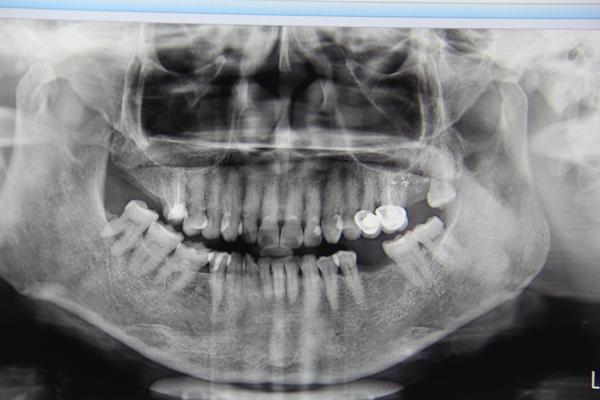

郑阿姨的牙齿拍片情况